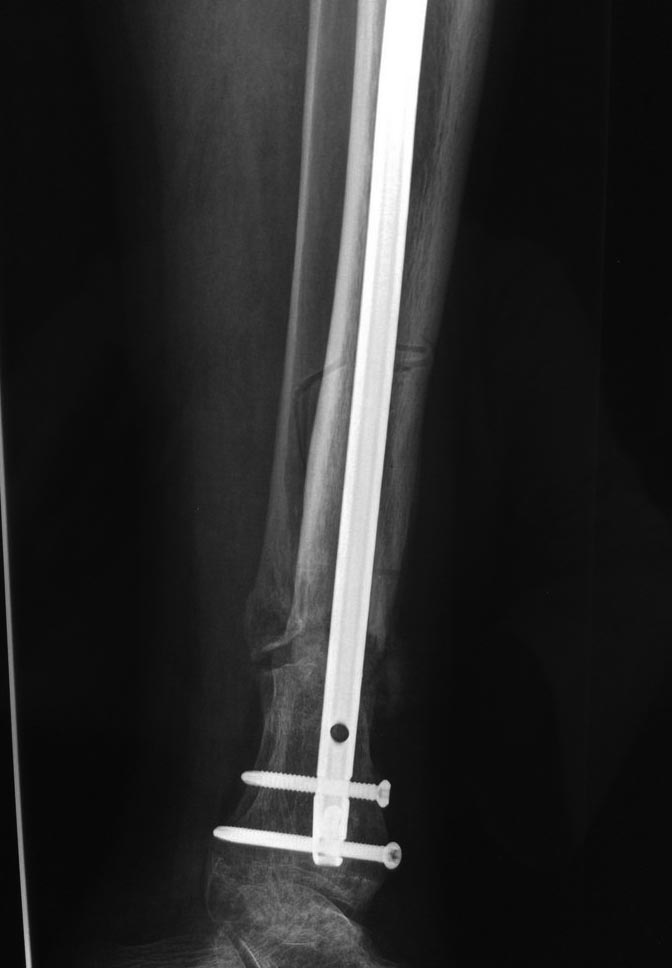

Уважаемые коллеги выразите Ваше мнение по следующему случаю. Молодой

человек, 27 лет, находится на лечении с диагнозом: Ложный сустав

большеберцовой кости в нижней трети, фиксированный интрамедуллярным

блокированным стержнем (12.02.2014 г), ложный сустав малоберцовой кости

в нижней трети левой голени, посттравматический артроз левого

голеностопного сустава 1 стадии. Укорочение левой нижней конечности на

В феврале 2014 г выполнил первым этапом: Фиксацию ложного

сустава в АНФ с восстановлением осей сегментов. Через семь дней БИОС с

рассверливанием.

После операции - вальгус голеностопного сустава. Гладкое течение

послеоперационного периода. Нагрузка по переносимости боли. Через 6

недель динамизация, через 2 недели стали мигрировать 2 фронтальных

винта. Пытался подкрутить, пришлось удалить.

Через 6 мес. контроль - линия ложного сустава прослеживается, но имеется

периостальная костная мозоль.

Не хватает стабильности.